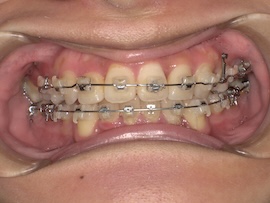

実際に処置をしてもらった直後の写真がこちらです。

まだ麻酔で感覚がないため、唾液が多く見えづらくてすみません。(笑)

意外と近くに埋まっていたそうなので、少し歯茎を切る程度で済んだみたいです。骨は削っていないので腫れもほとんどありません。

その後も歯茎を切った痛みは特別感じることなく、親知らずを引っ張ることに関しても今まで感じた歯の動く痛みと同じくらいでした。ただ全体的な痛みではないため反対側で普段通りの食事はできますし、覚悟していた分全然楽に感じます。(笑)

また、一度だけ歯磨き中に出血してしまって驚きましたが、少し裂けてしまっただけで特に問題ありませんでした。